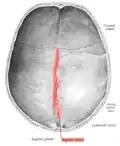

Animation. Sagittal suture shown in red. -

Sagittal suture seen from inside.